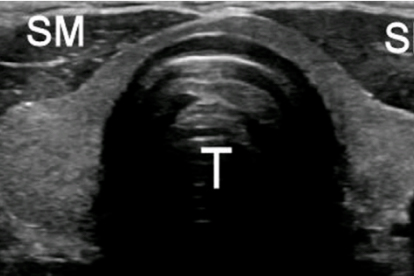

桥本氏病是一种常见的自身免疫性甲状腺疾病,主要表现为甲状腺功能减退。患者通常需要长期的内分泌治疗和定期随访,因此选择一家专业的内分泌科医院非常重要。

山东省立医院内分泌科是山东省重点专科,在甲状腺疾病诊疗方面具有显著优势。医院拥有完善的甲状腺疾病诊疗体系,能够开展甲状腺功能检测、甲状腺超声、细针穿刺活检等多项检查,为桥本氏病患者提供全面的诊疗服务。